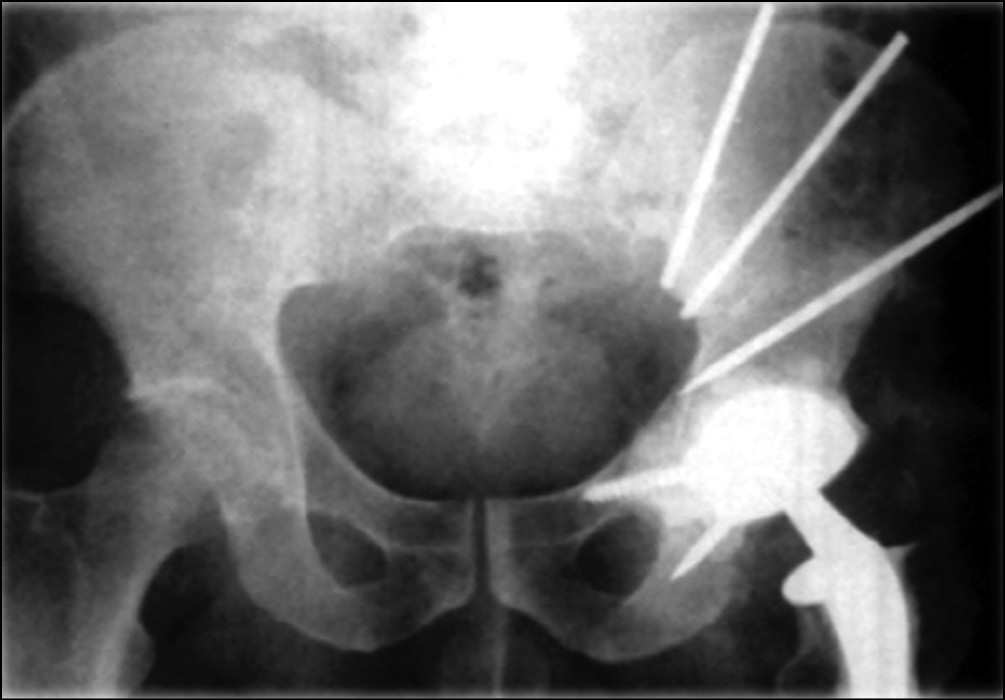

Реконструктивная онкологическая хирургия тазового кольца берет свое начало с 70-х годов прошлого века, когда J.T. Johnson выполнил двум пациентам с хондросаркомой параацетабулярной области реконструкцию вертлужной впадины после удаления опухоли путем проведения через оставшиеся лонную и подвздошную кости нескольких стержней и спиц, к которым при помощи костного цемента фиксировал чашку эндопротеза тазобедренного сустава (рис. 1).

Рис. 1. Рентгенограмма костей таза, реконструкция выполнена при помощи комбинации титановых стержней, костного цемента и эндопротеза тазобедренного сустава [39]

Первый пациент был жив через 5 лет после операции без данных о прогрессировании, мог ходить без средств дополнительной опоры. Второй пациент передвигался самостоятельно при помощи трости, однако через год после лечения у него выявлен рецидив опухоли, в связи с чем было рекомендовано выполнить МПБВ, от которого пациент отказался [15, 18].